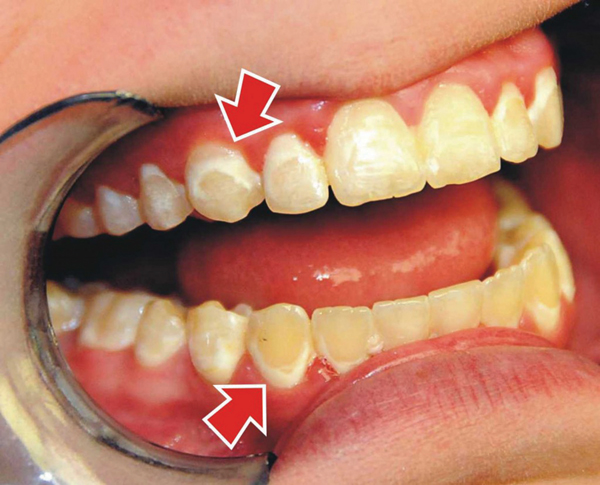

+ Cấu trúc của răng phức tạp như rãnh lõm, các lồi men vùng cổ răng, hay răng chen chúc lệch lạc tạo điều kiện cho mảng bám dễ tích tụ, khó làm sạch.

Viêm lợi cục bộ

Viêm lợi trong giai đoạn này chưa làm ảnh hưởng đến chân răng và những tổ chức quanh răng. Vì vậy người bệnh khi phát hiện mắc viêm lợi nên nhanh chóng chữa trị bởi khả năng khỏi dứt điểm là cao.